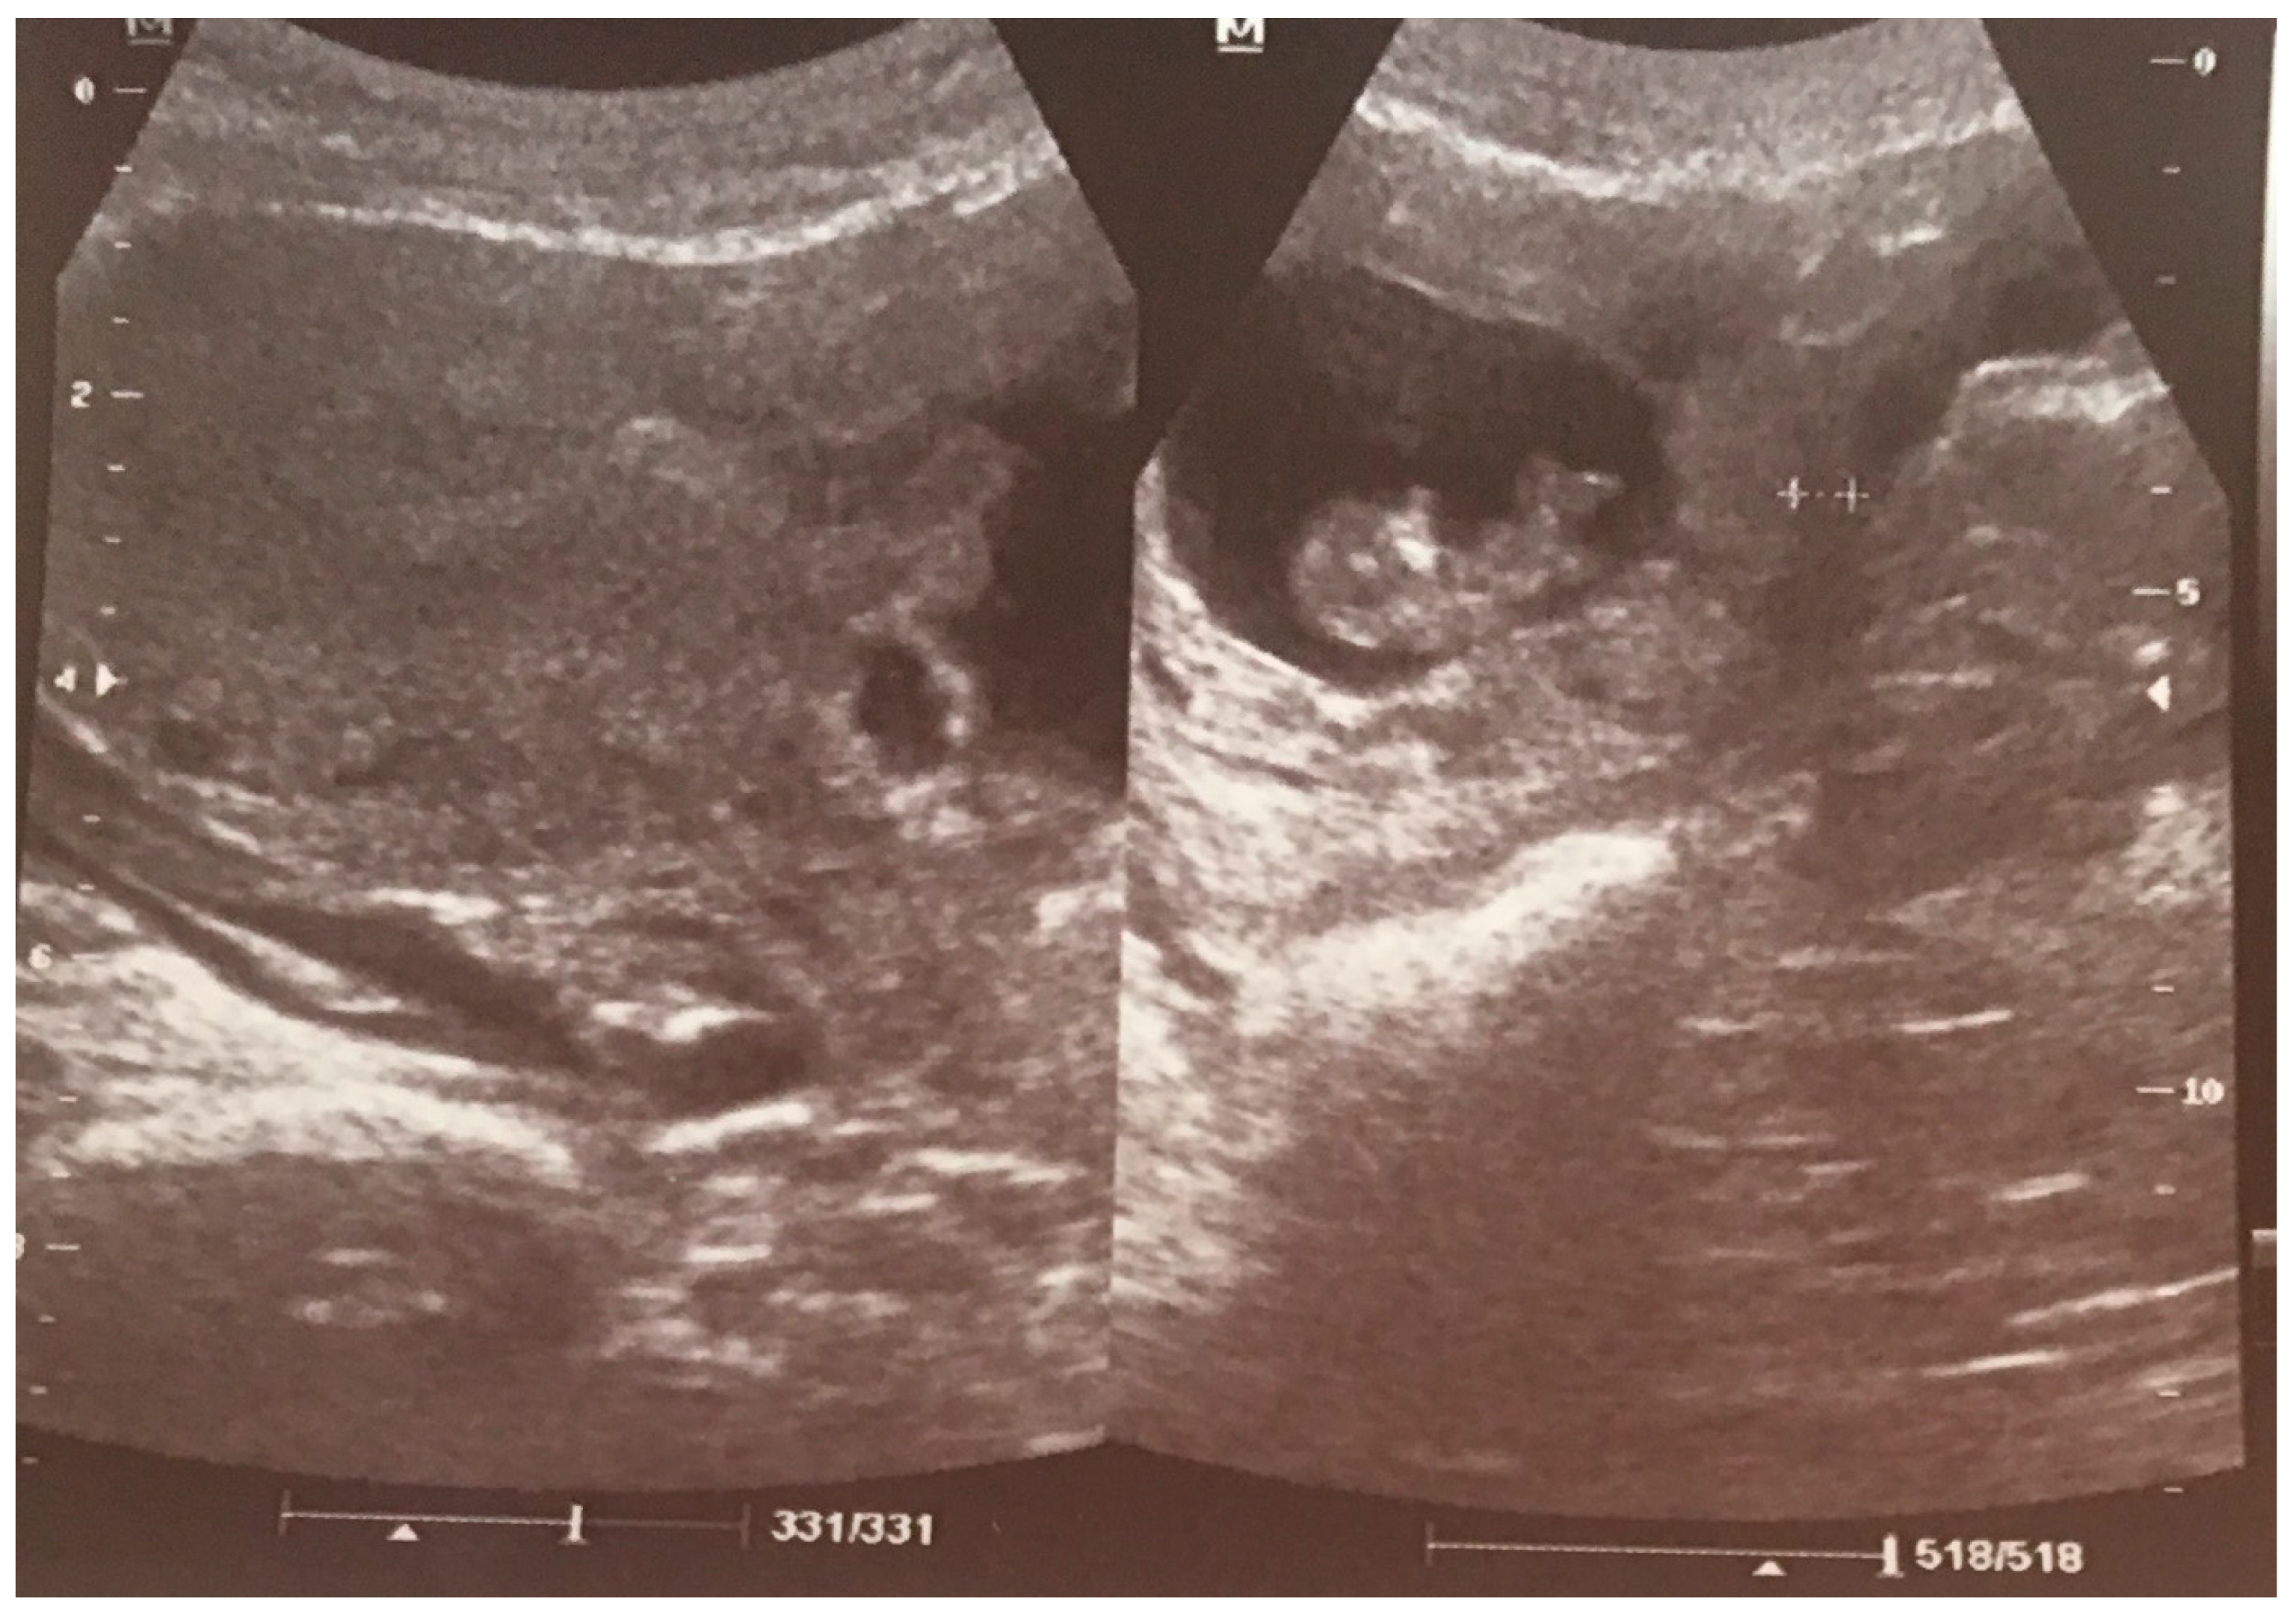

- 1

- an empty uterine cavity with clear endometrium and empty endocervical canal,

- 2

- the detection of a gestational sac within the anterior lower segment of the uterus embedded in the cesarean scar,

- 3

- an absent or thin (<5 mm) myometrium layer between the gestational sac and the bladder,

- 4

- 5

- the pathologies of the adnexa should be excluded, and there should be no detection of fluid in the Douglas pouch unless in the case of a massive hemorrhage or rupture of the uterus [5].

1.1. Case 1